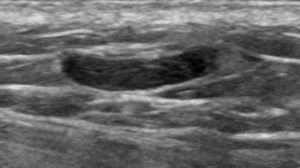

The spot magnification mammogram view and targeted ultrasound images that were performed at the site of palpable abnormality are shown here.

Explanation: Thrombophlebitis presenting as a partial or total thrombosis of a superficial vein in the breast is colloquially known as Mondor’s disease. Patients present with a cord-like palpable mass, often with local tenderness and skin erythema. Although the process is most commonly idiopathic, it can also be due to trauma or iatrogenic causes, or rarely, local breast cancer. Unless there is an identifiable ongoing cause, the condition is usually benign and self-limiting, and should be treated supportively with warm compresses and anti-inflammatory medication.

On our mammogram and ultrasound images, we can see the dilated and tortuous affected vessel. Although the vessel is abnormally hypoechoic under ultrasound due to the presence of thrombus, the presence of some color Doppler flow within the vessel indicates partial patency of the lumen.